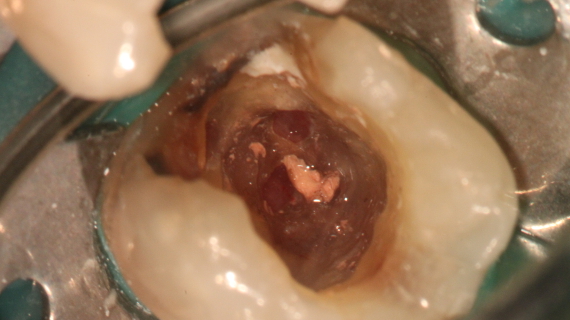

As lesões endo-perio representam um desafio para a prática clínica. Este tipo de lesões pode apresentar um misto de sinais e sintomas compatíveis com qualquer uma das disciplinas, o que pode induzir o clínico a um falso diagnóstico e a uma ineficaz abordagem terapêutica.

O diagnóstico pode ser difícil de executar devido às inúmeras vias de intercomunicação existentes entre a polpa e o periodonto e que podem levar a uma lesão combinada.

Infeção microbiana, fraturas, reabsorções e perfurações fazem parte do rol de etiologias possíveis para estas condições clínicas.